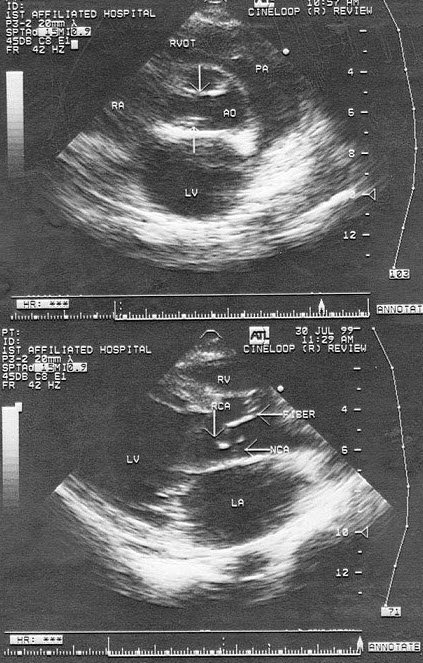

5、单项选择题

如图,初步超声诊断为()

A.二尖瓣返流

B.三尖瓣返流

C.主动脉瓣返流

D.肺动脉瓣返流

E.以上均不是

9、单项选择题

该病例最可能的诊断()

A.右室双出口并室间隔缺损

B.主动脉骑跨

C.室间隔缺损

D.大动脉异位

E.左室双出口